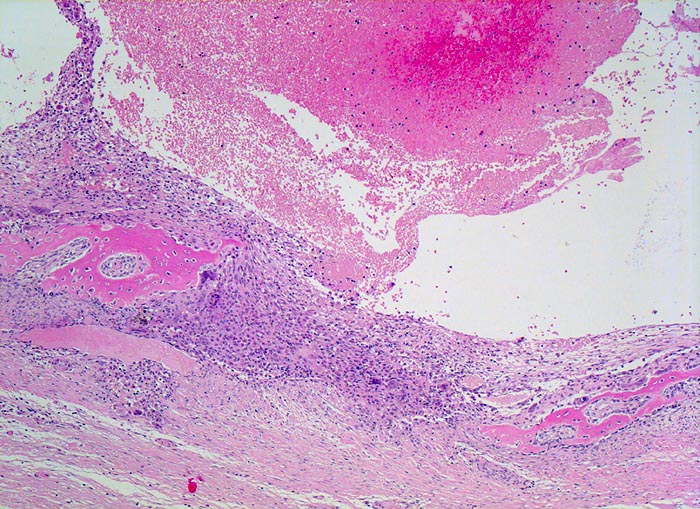

aneurysmatische Knochenzyste (AKZ)

Knochen, Fibula

In der Übersicht erkennt man einen pseudozystischen Hohlraum ohne Epithelauskleidung, welcher Erythrozyten enthält. Pseuozystenwand und $o{as16961Setpum} Septum enthalten Riesenzellen und mononukleäre Zellen. Daneben sieht man parallel zur Pseudozystenwand gelegen neugebildeten Faserknochen, welcher die Wand gleichsam "abstützt".

Lokalisierte Schmerzen und Schwellung in der proximalen Fibula. Im Röntgenbild ist eine Osteolyse erkennbar, die die betroffene Fibula auftreibt. Die Cortikalis über der Osteolyse ist hauchdünn.

Histologie

50